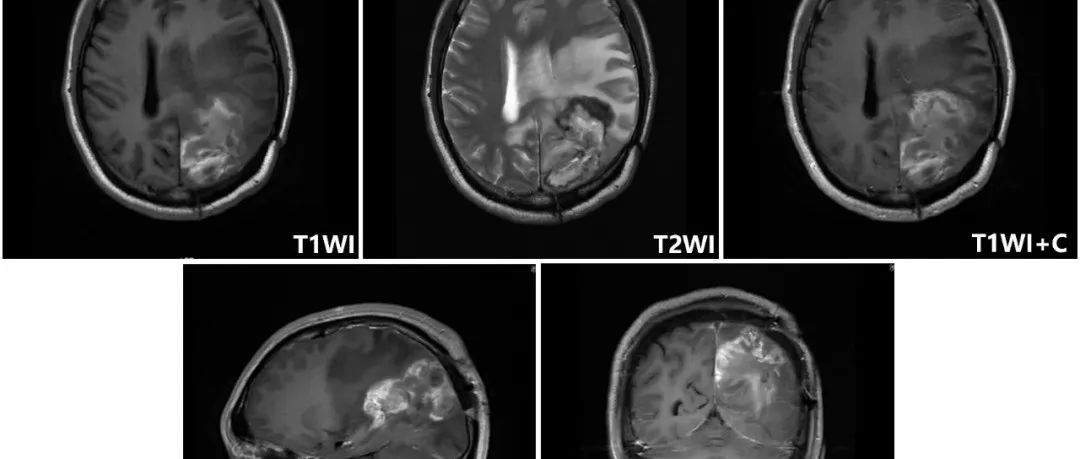

岩斜区脑膜瘤是起源于以岩-斜裂为中心的中上斜坡及三叉神经内侧岩骨的脑膜瘤。因岩斜区位置隐匿,解剖结构复杂,肿瘤压迫脑干与颅底神经及血管,被认为是神经外科最棘手的疾病之一。手术入路较多,术后肿瘤残留率高、患者预后差等现象目前仍然存在,术中一味地追求肿瘤全切也是导致术后高病死率、高致残率的主要因素。因此,术中根据肿瘤部位、性质给予患者制定个体化最佳手术入路选择,充分暴露肿瘤及周围重要结构,减轻脑组织牵拉,避免损伤周围神经、血管,减少术后并发症及新发神经功能障碍,在获得肿瘤高切除率的同时实现提高患者远期生存质量,是目前治疗的难点。...